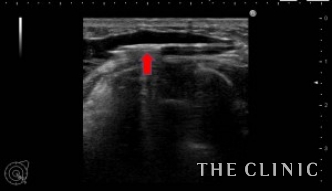

エコーで確認しながら、確実にヒアルロニダーゼ(ヒアルロン酸溶解剤)をしこり内に注入します。注入すると溶解剤とヒアルロン酸が反応して水のような液体になるため、すぐに吸引することができます。

こちらが吸引したヒアルロン酸です。